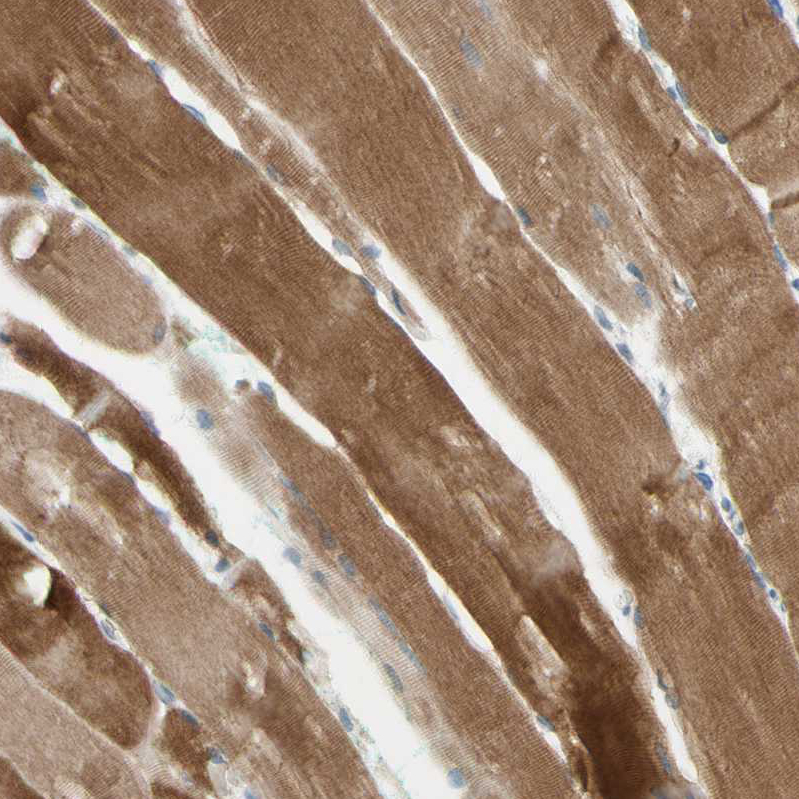

Immunohistochemistry analysis in human skeletal muscle and liver tissues using HPA008996 antibody. Corresponding JPH1 RNA-seq data are presented for the same tissues.